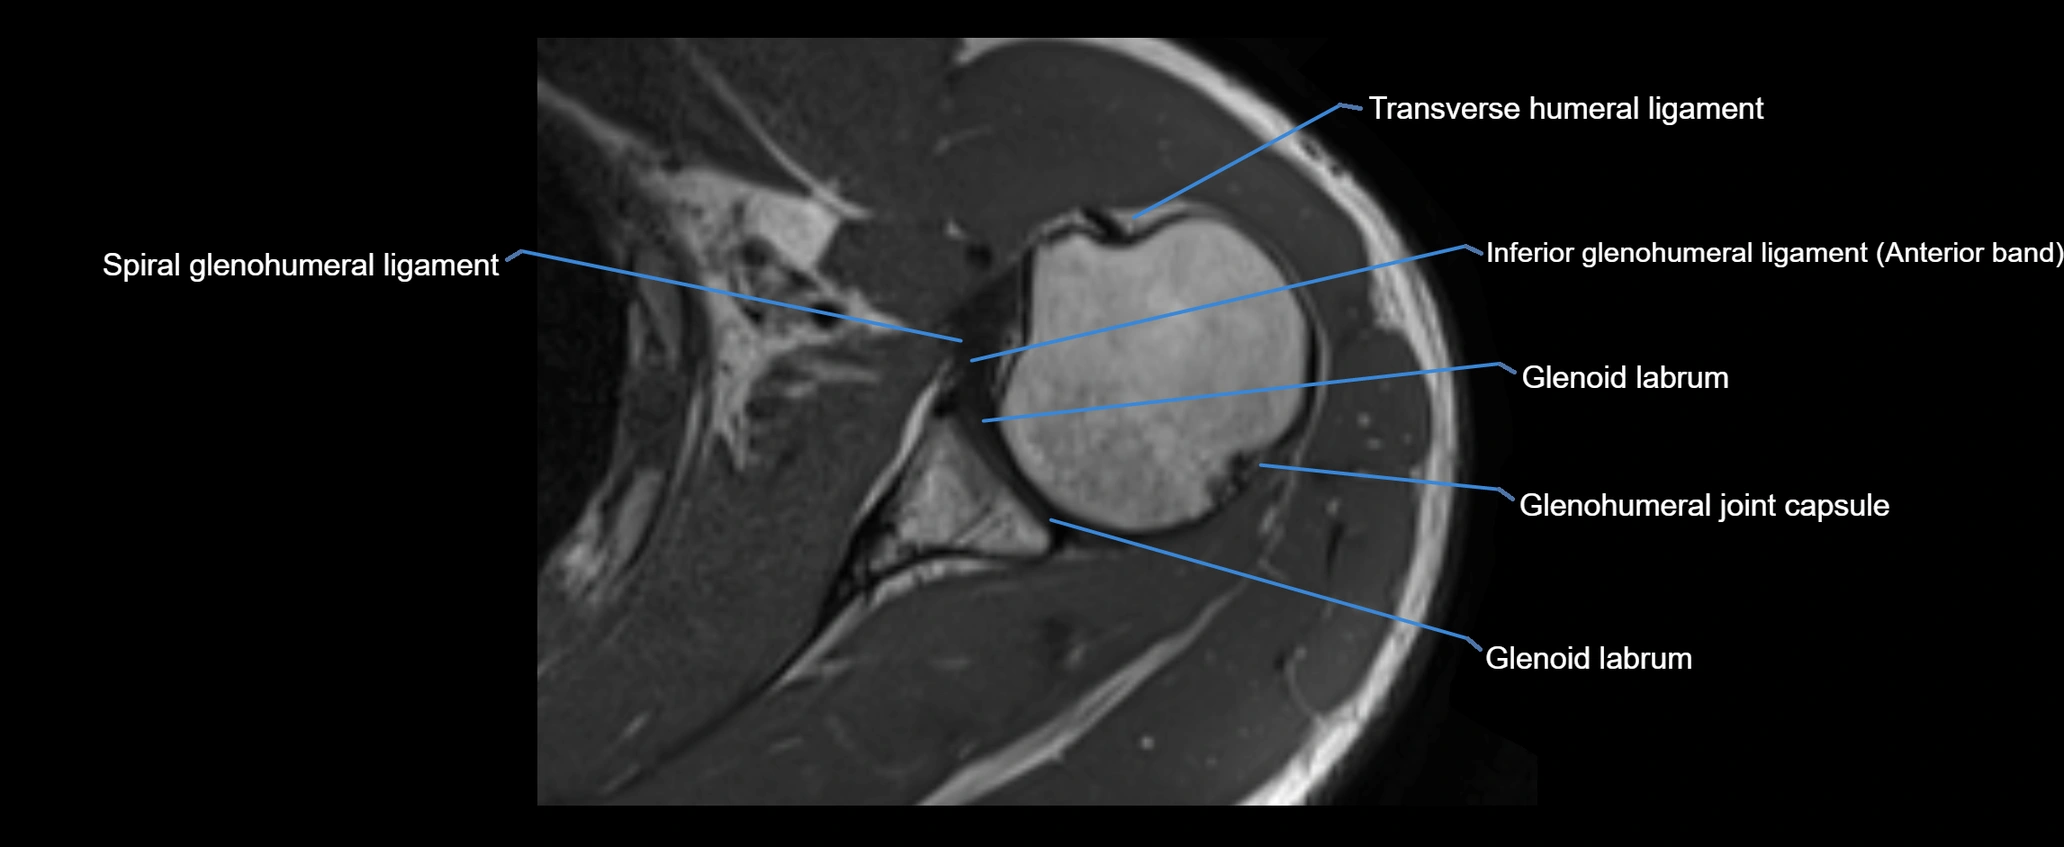

MRI images

image